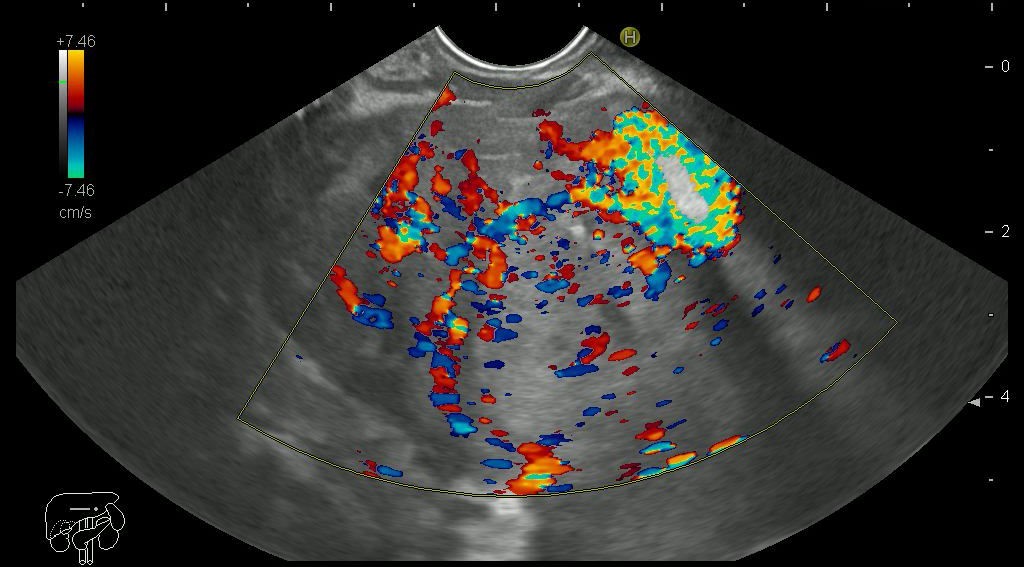

Evaluarea cu substanta de contrast foloseste un agent de contrast specific ecografiei (SonoVue), care in comparatie cu alte substante de contrast folosite la alte explorari imagistice (CT sau RM) are risc foarte scazut de a dezvolta reactii alergice, fiind aprobat pentru utilizare la pacientii cu probleme renale sau la copii. Ecoendoscopia cu substanta de contrast urmareste incarcarea cu contrast (vascularizatia) a leziunii examinate. In functie de modul de incarcare medicul poate diferentia leziuni maligne (cancere) de cele benigne, fiind posibila stabilirea diagnosticului bolilor pancreatice si a cancerelor peretelui digestiv, respectiv stabilirea corecta a indicatiei de punctie fina aspirativa sau bioptica.